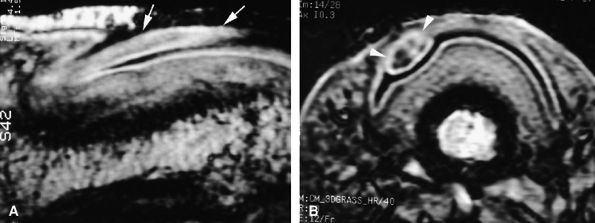

FIGURE 11.43 ● Acute open injury of the flexor pollicis longus tendon. (A) On these coronal post-contrast fat-suppressed T1-weighted images, the distal end of the tendon can be seen at the entry of the digital canal (arrows). (B) The proximal end is seen at the level of the radiocarpal joint (arrows). The tendon gap measures 6 cm. The empty tendon sheath shows significant synovitis (arrowheads in both images).

FIGURE 11.44 ● Acute rupture of the flexor digitorum profundus (FDP) tendon of the little finger in zone II. Coronal (A) and axial (B) post-contrast fat-suppressed T1-weighted images show retraction of a flexible proximal end (arrows) wrapping around the FDS tendon (asterisk).